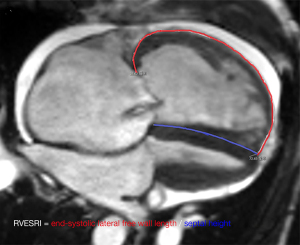

RVESRI is the ratio of the lateral free wall length to septal wall height in the end-systolic phase (5) and was independently measured on the long-axis 4-chamber cine image of CMR (Figure 2) by 2 residents with 5 years of experience on the picture archiving and communication system. After one month, the measurement of RVESRI was repeated by one resident. Moreover, the right ventricular eccentricity index (RVEI) (9) was also calculated on short-axis cine images at the mid ventricular level of the right ventricle in the end systole by one resident with 4 years of experience.